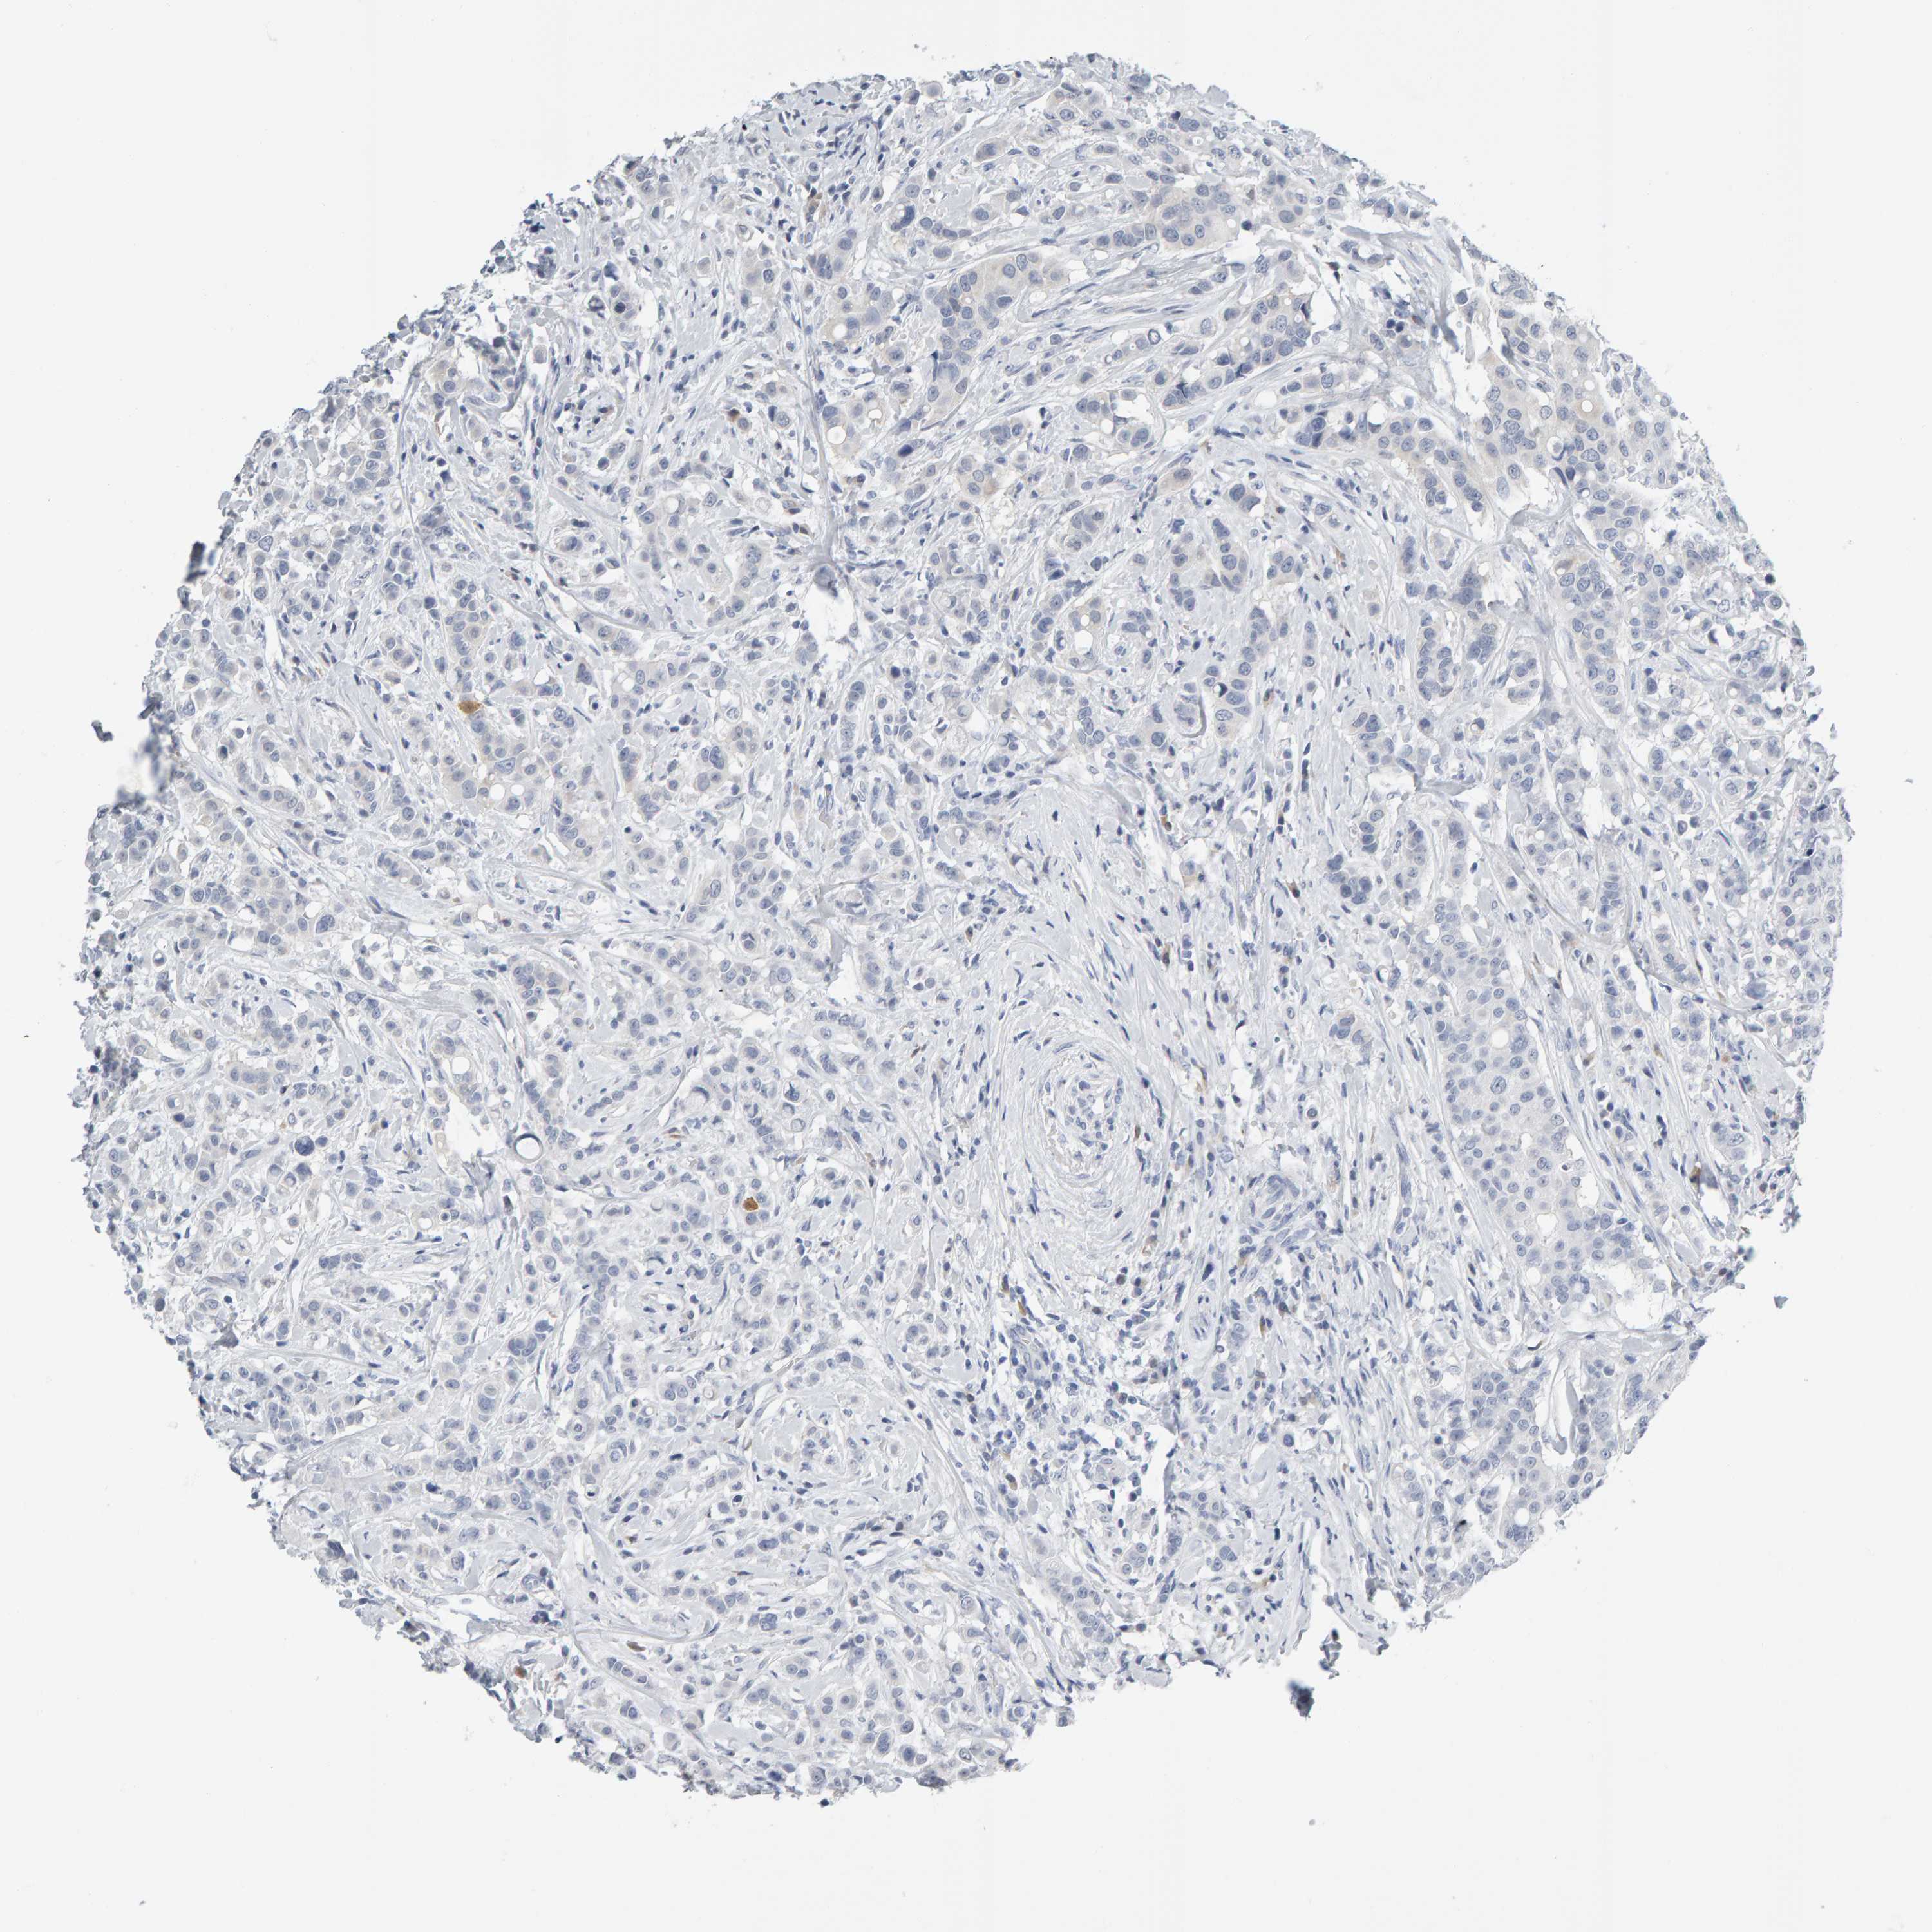

BRCA TCGA BRCA VALIDATION PROTEIN EXPRESSION

ANTIBODIES

AND

VALIDATION